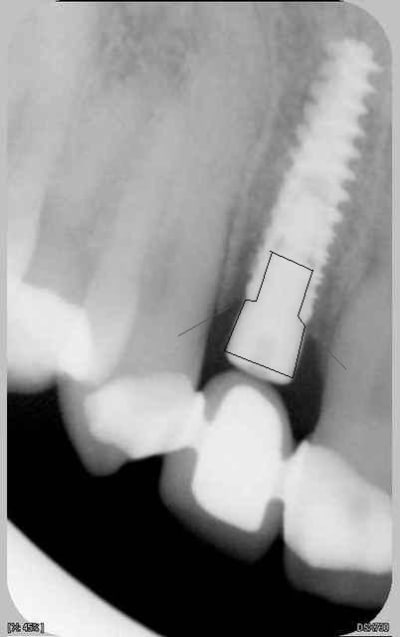

nouvelle radio cette semaine

c'est des krestals? Ça n'a pas l'air dramatique sur la radio. Une petite caractérisation qui me parait logique vu la connexion.

> c'est des krestals? Ça n'a pas l'air dramatique sur la radio. Une petite

On n'a pas les mêmes critères d'exigences. Perdre 4 mm d'os sur 12 soit 1/3.

Attends, sur ces radios t'as 4 mm de perte osseuse? Les vis de cicatrisation sont en place non? Je devine la jonction implant/vis et y a quasiment pas de perte sur tes dernières radio. Enfin je connais pas bien le krestal et la forme de la vis.

Je veux dire, elle est où la perte osseuse sur cette radio? Mais tu as raison, on ne doit pas avoir les même exigences.

chatondecarte écrivait:

La cratérisation est visible beaucoup plus haute: surtout au sondage. L'os que tu vois est en palatin, en vestibulaire, il n'y a plus rien sur cette même longueur.

Sur la molaire, tu ne vois rien aussi.

Je disais juste que je ne voyais rien d'affolant sur la radio, mais bien sur si tu as 4mm au sondage, c'est ça qui prime.